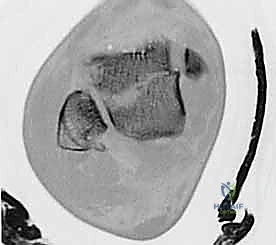

3. التصوير المقطعي المحوسب (CT Scan) - المعيار الذهبي

في عيادة الأستاذ الدكتور محمد هطيف، يُعتبر التصوير المقطعي المحوسب ثلاثي الأبعاد (3D CT Scan) إجراءً روتينياً وحتمياً لأي كسر في عظم الكاحل. توفر الأشعة المقطعية تفاصيل دقيقة للغاية عن خطوط الكسر، مدى التفتت (Comminution)، وحجم الإزاحة المفصلية التي لا يمكن رؤيتها بالأشعة السينية العادية. بناءً على هذه الصور، يقوم الدكتور هطيف ببناء استراتيجية الجراحة (أين سيفتح، ما نوع الشرائح والمسامير التي سيستخدمها، وكيف سيعيد بناء العظم).